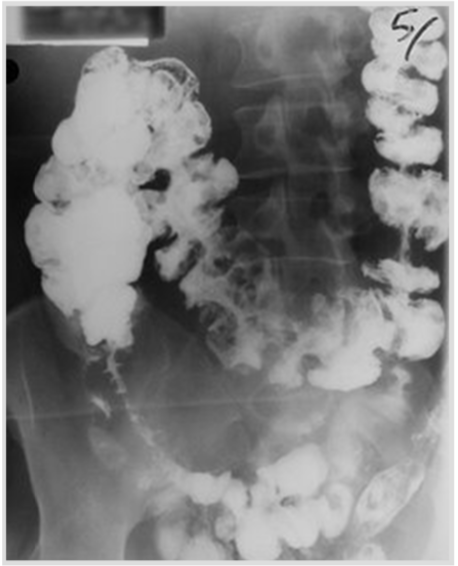

a 19 year old boy presents with finger clubbing, weight loss, watery diarrhea and a mass in the right iliac fossa. A barium enema of the gastrointestinal tract was performed, and findings were as below. What is the likely diagnosis?

Crohn’s disease

Note: the presence of strictures is noted in the barium enema, a characteristic of Crohn’s (string sign)